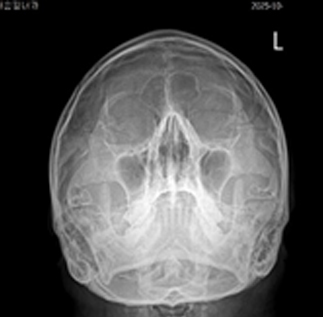

만성기침의 가장 많은 원인인 분비물이 목 뒤로 넘어가는 후비루 증상이 있는 상기도 기침 증후군인데, 비염, 부비동염이 원인인 경우가 많습니다.

후비루 증상은 부비동 엑스레이나 비강 내시경을 통하여 비부비동염 여부를 확인해야 하며, 기침형 천식은 기관지 유발 시험, 호기 산화질소, 객담 호산구 검사 등으로 진단할 수 있습니다. 한편 위식도 역류 질환은 식도로 역류된 위속의 내용물로 인해 불편한 증상이나 합병증이 유발되는 상태를 말하며, 24시간 식도 산도 검사나 위내시경을 통하여 진단할 수 있습니다. 위산이 식도를 넘어 인두와 후두까지 역류하여 점막을 자극하는 경우 후두 내시경을 통하여 인후두 역류 질환을 진단할 수 있습니다.

상기도 기침 증후군 기침형 천식 위산 역류 질환

치료 전 기관지 유발 시험 검사 위식도 역류 질환

img img img

치료 후 기관지 유발 시험 검사 양성 인후두 역류 질환